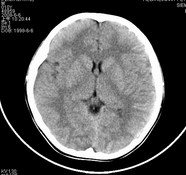

标题: PED0853:M10Y,右侧脑室颞角?

男,10岁,因近来常头痛就诊。先平扫拟诊右侧脉络膜裂囊肿,后薄层(3mm)扫描见此灶与右侧脑室后角相通,且向内几乎与鞍上池相连,并见一血管影沿其走形 (可能是脉络膜前动脉)。1。请教:脉络膜裂或脉络膜裂囊肿与侧脑室颞角或鞍上池相通吗?好像谁说脉络膜裂是脉络膜从外侧裂向侧脑室移行的裂隙。请高手讲讲这点的解剖关系。2。建议:对于老年患者,有丘脑附近特别是右丘脑附近的近似腔隙性梗死灶,临床症状不明显的,应做3mm薄层扫描,看病灶向下是否与侧脑室颞角相连,以免误诊。

应该是侧脑室下脚.

侧脑室下角

侧脑室下角;扫描位置不标准。